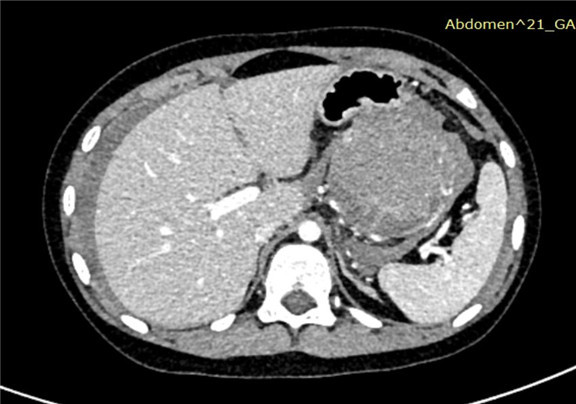

上腹部增强CT:胰尾部占位性病变,考虑胰腺尾部肿瘤并破裂出血,以胰母细胞瘤可能性大,不除外胰腺实性假乳头状瘤,肝周积液、积血,符合肿瘤破裂所致。

术前CT检查:

动脉期

静脉期